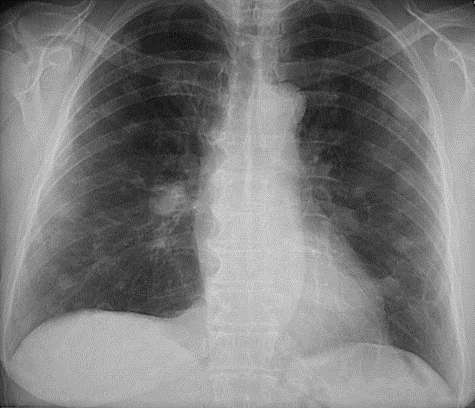

What’s your diagnosis?

List the 3 most common conditions responsible for this appearance.

Cannon ball metastases

Commonest primary sites: Breast > colon>renal